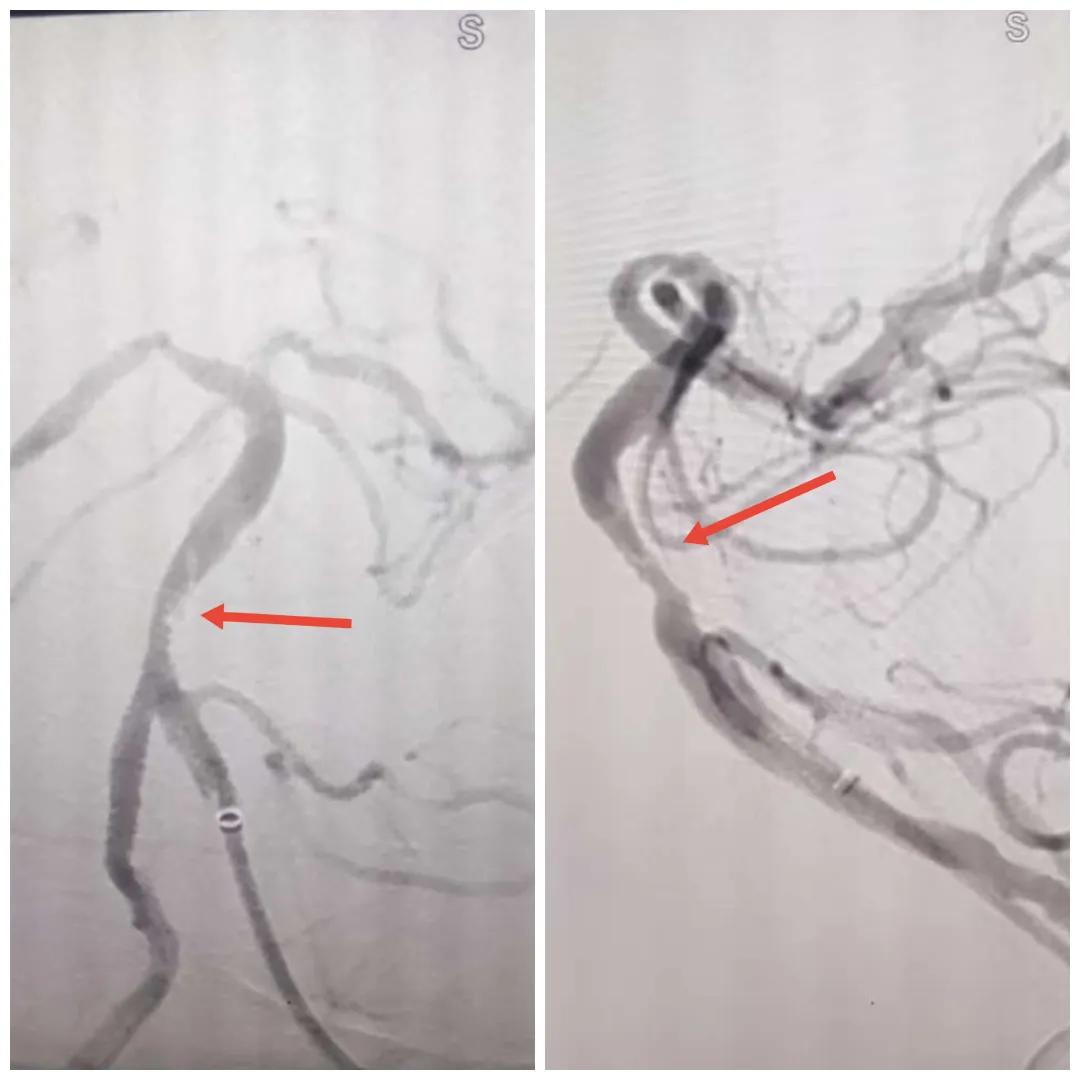

在經(jīng)造影后,主刀醫(yī)生腦一科副主任楊慶堂發(fā)現(xiàn)患者基底動(dòng)脈下段重度狹窄且狹窄段以遠(yuǎn)有大負(fù)荷血栓,其狹窄處考慮為動(dòng)脈夾層,手術(shù)難度及風(fēng)險(xiǎn)較大。楊慶堂副主任在彭壯副主任醫(yī)師的協(xié)助下運(yùn)用spaceman(太空人)技術(shù),中間導(dǎo)管抵近血栓抽吸配合支架拉栓,成功開通血管。再次造影可見基底動(dòng)脈管腔明顯增寬,遠(yuǎn)端血管顯影良好,且等待20分鐘后造影仍顯示血流通暢。楊慶堂副主任考慮到本次手術(shù)時(shí)間不宜過長,現(xiàn)患者基底動(dòng)脈及分支前向血流維持良好,給予其抗栓藥物應(yīng)用后結(jié)束手術(shù),并建議患者3個(gè)月后復(fù)查造影,明確其基底動(dòng)脈夾層情況。

造影可見血管夾層和大量血栓形成

取栓后血管管腔增寬,前向血流良好